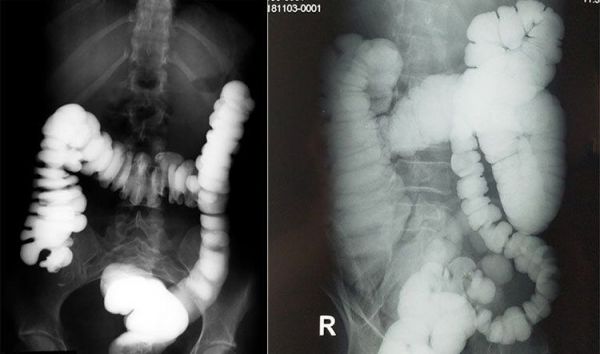

大肠钡剂灌肠造影 了解大肠的长度和形态

由于便秘存在多种类型,一般需要针对性采用不同检查方法进行鉴别和诊断。排粪造影,指的是使用 钡糊(一种影像学对比剂)直肠内注射模拟粪便,并通过影像 学观察 和分析患者整个排便的过程,从而评估排便相关盆底肌、直肠肛门及周围组织等排便活动中不同时间段的功能和重要解剖学参数变化的一种检查方法。磁共振排粪造影的优点是该检查可以进行实时动态的观察记录并且没有辐射,推荐用于怀疑为排便功能障碍型便秘患者的辅助检查,特别适用于存在形态和解剖学改变的便秘。排粪造影检查常常联合结肠传输实验、直肠肛门测压、球囊逼出实验等方法,用于慢性便秘的准确分类和分度,以便临床医生更为全面的掌握病情,制定更为合理的治疗方案。

排粪造影